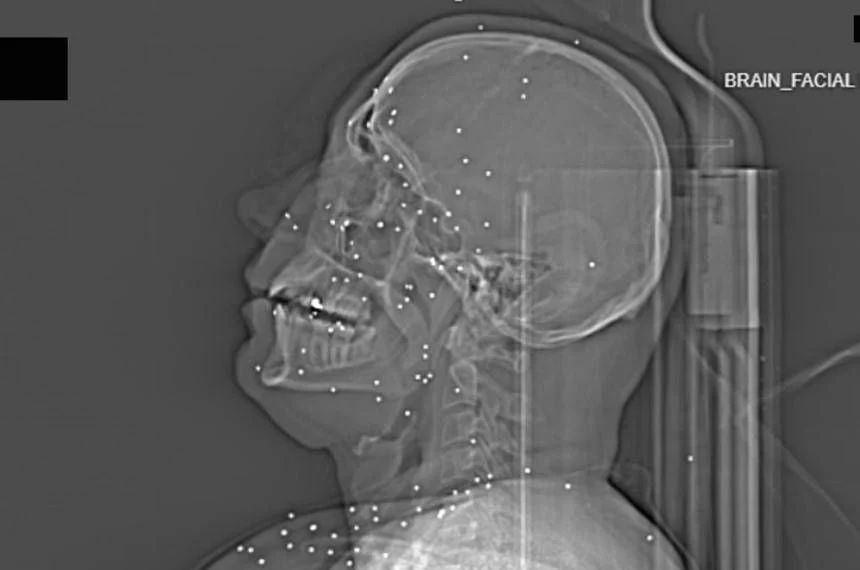

Entre os casos analisados há o de "Anahita" (nome fictício), uma jovem pouco mais que vingtenária. Suas imagens mostram múltiplas pequenas esferas metálicas, de 2 a 5 mm, dispersas pelo rosto, nas órbitas oculares e até numa área encefálica. São projéteis do tipo birdshot — perdigões de caça — que, disparados a curta distância, não representam ferimentos leves: estilhaçam ossos, destroem tecidos moles e frequentemente resultam na perda ocular. Anahita perdeu ao menos um olho, possivelmente os dois.

O painel de avaliação foi composto por especialistas internacionais — médicos de emergência, radiologistas, peritos em imagens de trauma e balística — e incluiu a consulta a um ex-médico de pronto socorro iraniano. A conclusão técnica é consistente: o software dos exames não apresenta sinais de manipulação evidente e as imagens, no conjunto, apontam para um padrão de tiro que incide sobre olhos, tórax e genitais. Em termos forenses, a repetição desse padrão sugere mais do que abuso isolado: denota uma intenção de matar ou de produzir incapacidades permanentes.